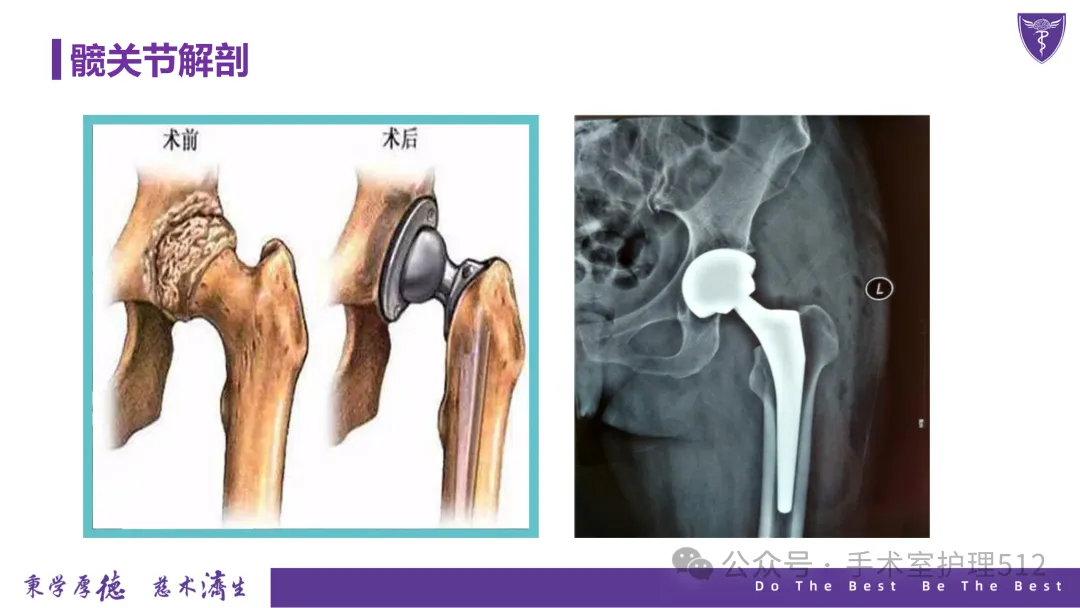

【PPT】全髋关节置换患者围术期的护理

该PPT具体描述了全髋关节置换患者的围术期护理,以我院的一例具体病例介绍,围绕髋关节患者的术前护理、术中手术配合、术后护理以及康复锻炼、并发症的预防等展开介绍,尤其侧重介绍手术室工作内容,髋关节置换术的手术配合,从术前物品准备、术中巡回护士、洗手护士的配合工作,以及术后的护理重点分类做了详细介绍。此类PPT也有助于手术室的临床教学工作,帮助新入职员工在入职初期学习掌握专科知识。